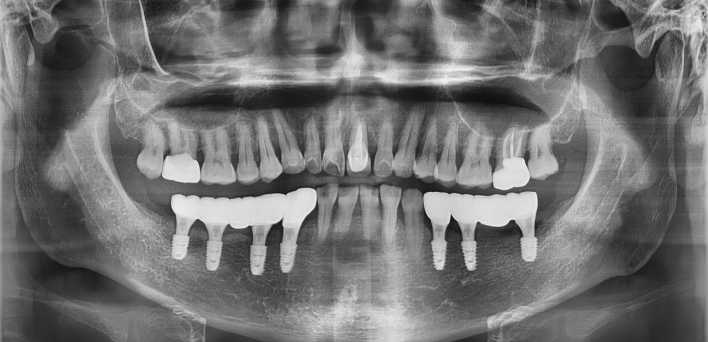

임플란트 : 손 ** 님 (50대)

치아가 있다는게, 아직도 정말 꿈만 같아요.

Before Before

2020.02.30

After After

※ 더서울치과의원은 의료법을 준수하며 위 케이스는 실제 환자의 동의를 얻은 사례로 치료 전, 후가 동일한 환경에서 촬영되었습니다.

환자 케이스에 따라 부작용이 발생할 수 있습니다. 이 부분은 의료진의 충분한 상담과 체크를 통해 예방하고 줄일 수 있습니다.

[임플란트 부작용] 수술 후 관리가 소홀할 경우 출혈, 주위염 등의 부작용이 발생할 수 있어 구강 위생을 철저히 유지하고, 정기적인 검진을 통해 상태를 점검하는 것이 중요합니다.

환자 특징

환자 특징01무치악 상태

환자 특징02수년간 무치악으로 지내심

임플란트가 불가능할것이라

생각하고 내원

위, 아래 6개씩 식립

디지털 풀아치 임플란트